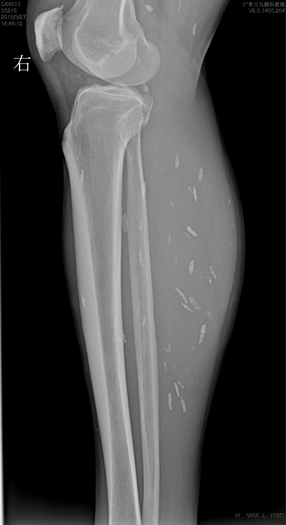

右小腿X光片,见肌肉内多发囊虫病灶。